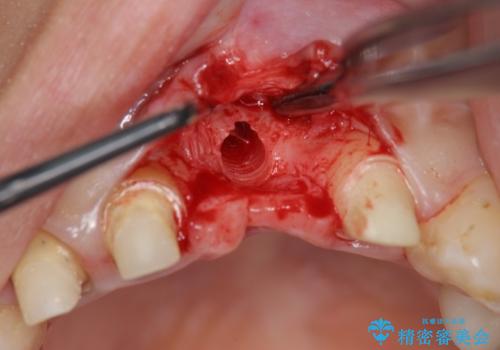

不良インプラントを除去し最終的にブリッジによる補綴で審美性の改善を行うこと、その準備として骨の造成・歯肉の移植による歯の欠損部顎堤のボリュームを維持・増大を計画します。

より審美的な改善を強く求められたため、インプラントを除去し可及的に欠損部顎堤を増大したのちブリッジによる審美改善を行いました。